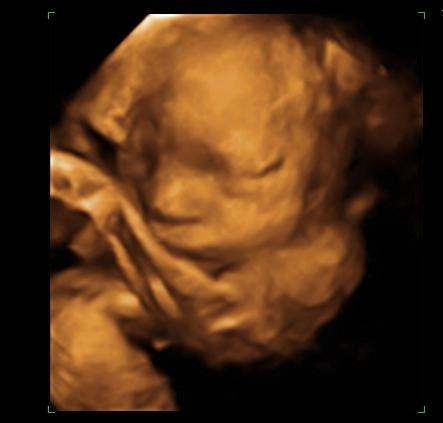

Så blev det endelig vores tur til scan igen, nøj det var jo bare vildt!!!

Orhh....hvor er mors lille <---- ( ? ) klump dejlig, nøjh nogen dejlig kinder.

Han blev målt til at jeg skulle være 1 uge længer fremme, men det kunne snyde op til 10% sagde hun.

Vægten sagde 1193.g